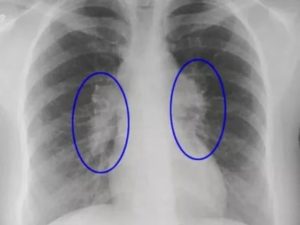

В диагностике используют:

- рентгенологическое исследование легких (лучше компьютерную томографию, если есть возможность);

По результатом обследований наблюдаются фиброзные очаги (тяжи, рубцы) и значительное снижение функции легких.

Для диагностики фиброза также используют рентгенологические методы:

- рентгенограмма необходима для визуализации легочного рисунка,

- компьютерная томография дает возможность увидеть очаговые, периферийные, субплевральные, сетевидные затемнения органа,